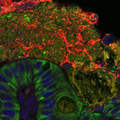

A Germinated Microsporidian Spore in Close Proximity to the Host Cell Surface

Transmission electron micrograph shows a germinated microsporidian spore adjacent to a host cell, with a polar tube extending to transfer sporoplasm into the host cytoplasm. The study identified EnP1, a nucleus-targeted effector secreted by microsporidia, which enhances their proliferation by interacting with host histone H2A and inhibiting ferroptosis. This research highlights how microsporidia alter host cell functions through secreted effector proteins, ultimately facilitating their own survival and contributing to disease progression. Guan et al. 2026

Image Credit: Bing Han